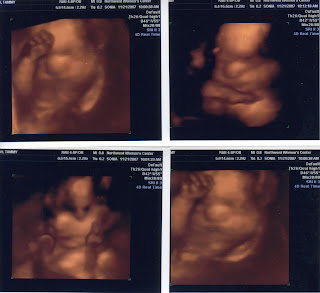

Caleb's 4D pictures are here!!!

The much anticipated 4D ultrasound has been performed and wouldn't you know it? We've got a "shy" baby boy. Throughout the procedure, he had his hands and arms covering and all around his face. There is actually one picture where it looks as though he was in Houston traffic, if you know what I mean. Anyway, here are the pictures. The video is really neat as well but it may take some time to figure out just how to post that one. We love you all and hope you enjoy the pictures.

This past Tuesday (Dec. 11th), Tammy had a 31 week checkup and we returned to try for some better pictures of our "shy boy". Well, apparently, there's even less room in the womb, than before. For these pictures, Caleb was obscuring his face with not only his hands, but his feet as well. Looks like we'll just have to wait until the delivery.